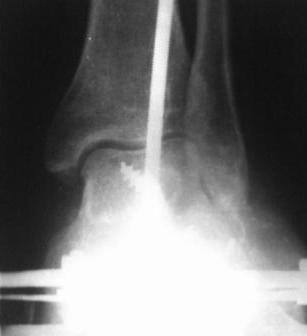

Больной 1964 г.р. С 30.08-по 14.09.07г. лечился в г. Иркутске, в МУЗ Медсанчасть ИАПО с д-зом - Кататравма. З/осколчатый в/с перелом обеих пяточных костей со смещением. З/компр, перелом тела L-2 п-ка 2-степ, неосложненный. Произведено скелетное вытяжение по Каплану, но больной до конца не лечился, от операции отказался, наложена гипсовая лонгетная повязка и выписан.( из выписки и/б ) К нам обратился с жалобами на деформации стопы, боли при ходьбе. Ходит при помощи костылей. Наш план, учитывая наличие подтаранного артроза с болевым синдромом - подтаранный и пяточно-кубовидный артродез с коррекцией варусной деформации.Уважаемые коллеги, помогите советом

Уважаемые коллеги, всем большое спасибо!!!

28.02.08г. произведен трехсуставной артродез таранно-пяточного, таранно-ладьевидного и пяточно-кубовидного суставов, с клиновидной остеотомией пяточной кости, с заполнением синуса костными осколками. Фиксация таранно-пяточный стягивающим винтом, таранно-ладьевидный и пяточно-кубовидный спицами, варусная деформация стопы устранена. Для наблюдения за состоянием раны и стопы а также для фиксации и поддержания напряжения произведен к/остеосинтез аппаратом Илизарова.

Почему не сделал чисто подтаранный артродез? Потому что и так нарушена биомеханика стопы, после подтаранного артродеза еще больше нарушается, особенно в суставе Шопара, поэтому артродезировал и его.

1. артродезировать задний(за исключением голеностопа) и средний отделы стопы в один этап - насколько это оправдано у пациента 43 лет, при том что на представленных преоп. рентгенограммах таранно-ладьевидный сустав сохранный?

2. Угол пяточной инклинации остался близким к горизонтальному,что за остеотомия была?

3. Из-за отсутствия продольного свода стопы и выполненных артродезов весьма вероятно быстрое развитие остеоартроза голеностопного сустава... что будете предлагать пациенту тогда?

1.Это тройной артродез и эта операция делается в один этап независимо от возраста, на пред/опер Р-грамме да и клинически имеется артроз таранно-ладьевидного и пяточно-кубовидного суставов с болевым синдромом,( из анамнеза плоскостопие 2-степ.)

2.Угол пяточной инклинации был и правда "остался" как было до операции, требование б-ного исправить только варусную деформацию, чтобы мог одеть обуви, правильно и б/болезненно наступать ногу, на одновременной исправлении плоскостопии несогласился.

Произведена клиновидная остеотомия пяточной кости, с обрашением основания клина кнаружу по скиаграмму из Рент аксиальной проекции.